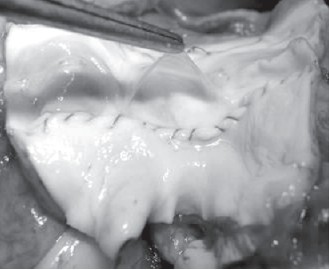

Клеточные компоненты, не принимающие участие в миграции и росте аутологичных клеток в экстрацеллюлярном матриксе, должны быть удалены с биологического материала, предшествующего производству матрицы. Кроме того, эти клетки обладают иммунной активностью и могут служить переносчиками заболеваний от донора реципиенту. Данный процесс носит название децеллюля- ризации (рис. 3).

Рисунок 3. Децеллюляризированный клапан овцы после эксплантации. Макроскопическое исследование показывает сохранившуюся состоятельность створок клапана, отсутствие дегенерации, признаков кальцификации и инфекционного поражения.

В нашей лаборатории при клинике кардиоторакальной трансплантологии и сосудистой хирургии Ганноверской высшей медицинской школы были разработаны и активно используются методы децеллюляризации на основе детергентов [31]. «Ганноверский метод» включает использование смеси двух детергентов: додецилсульфата сульфата (SDS) и деоксихолата натрия (SD) [32]. Эффективность удаления клеток из ткани контролируется стандартными методами окрашивания гематоксилином и эозином и анализом клеточного ДНК. Для оценки прочности и функционального статуса таких клапанов сердца были выполнены серии имплантаций на овцах [33] (рис. 3). I. Tudorache и соавт. для изучения механофизических характеристик были проведены различные биомеханические тесты [34]. Оценивались образцы легочного клапана для оценки структурной жесткости, предела прочности, конечной деформации и модуля упругости (модуль Юнга). Растяжимость образцов проверялась с помощью бесконтактного лазерного микрометра. J. Zhou и соавт., сравнив несколько способов децеллюляризации свиных клапанов, показали, что деоксихолат натрия является оптимальным детергентом для удаления клеток и презервации матрикса [36].